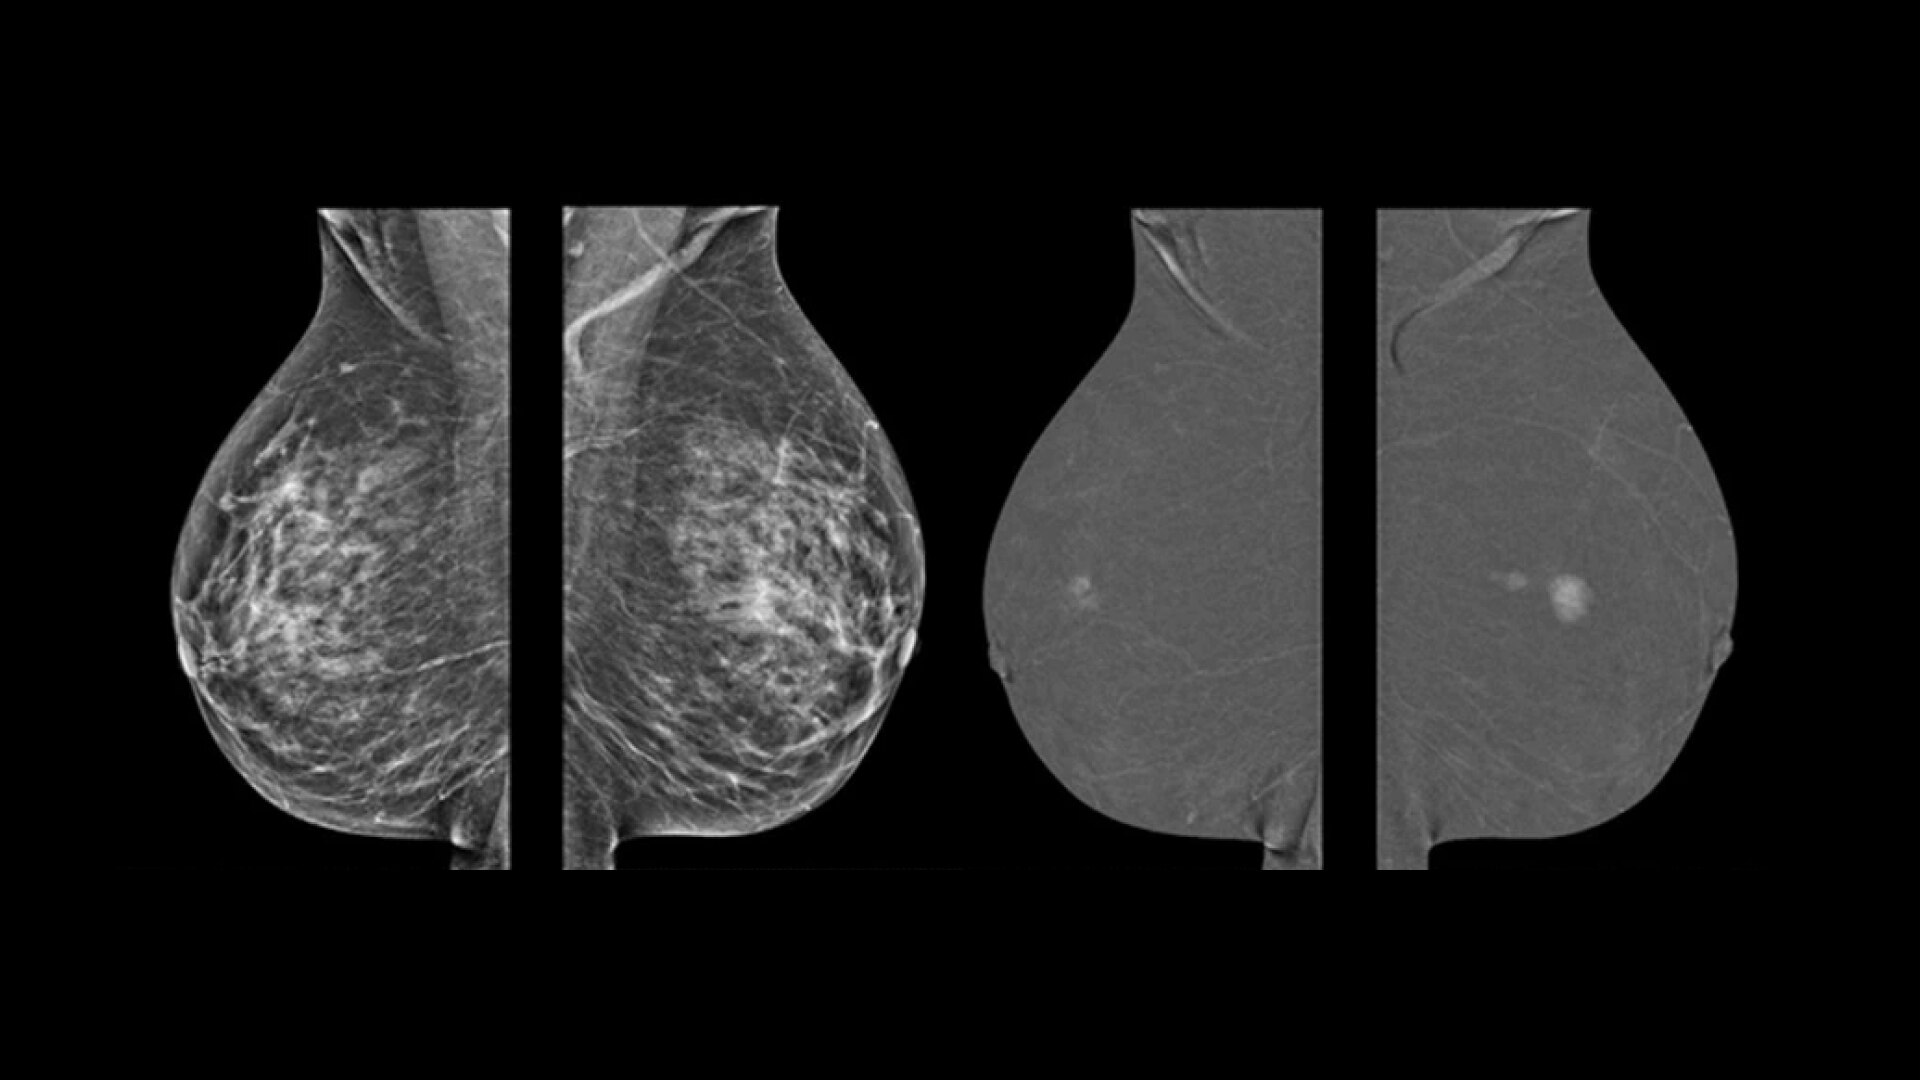

Early Detection

Critical Answers Sooner

Complex cases come with enough uncertainty. That's why the Voluson Expert 22 is specifically designed for in-depth assessment of complicated anatomy — with pioneering first trimester, fetal cardiac, gynecological, and other pivotal technologies that focus on early detection and intervention.